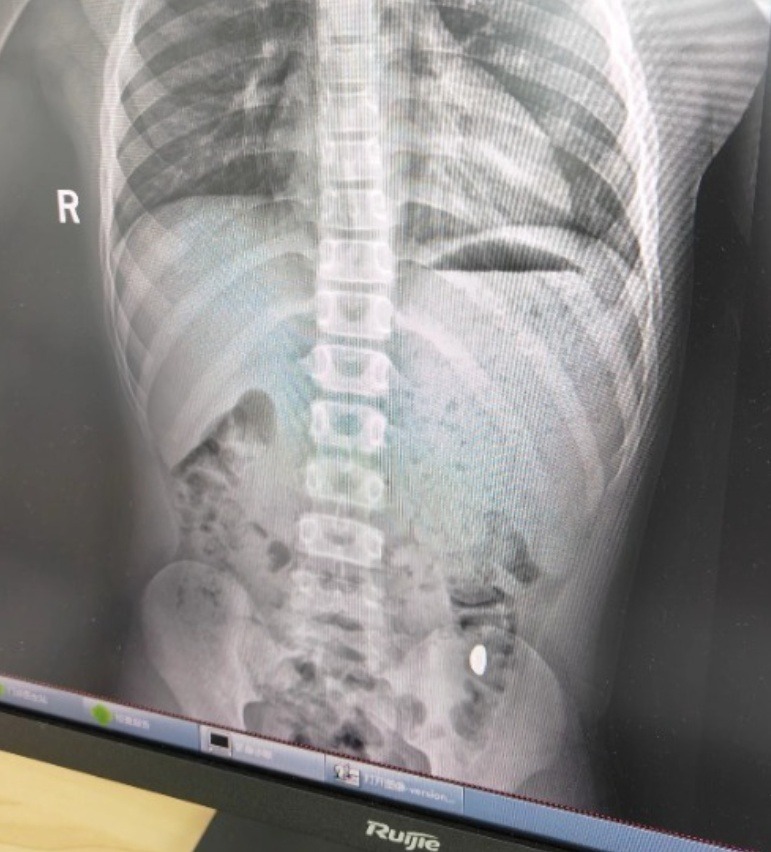

Hồ sơ khám tại Bệnh viện Nhân dân số 5, thành phố Côn Sơn (Tô Châu) ghi nhận bệnh nhi nuốt nhầm khoảng 10 gram vàng, đã đi vệ sinh 2 lần nhưng chưa thấy vàng. Hiện tại không có đau bụng hay nôn ói, chẩn đoán cho thấy còn dị vật trong dạ dày. May mắn là, sau khi thăm khám buổi sáng, ngay buổi chiều hôm đó, vàng đã được thải ra ngoài.

Ảnh chụp X-quang của cậu bé nghịch ngợm